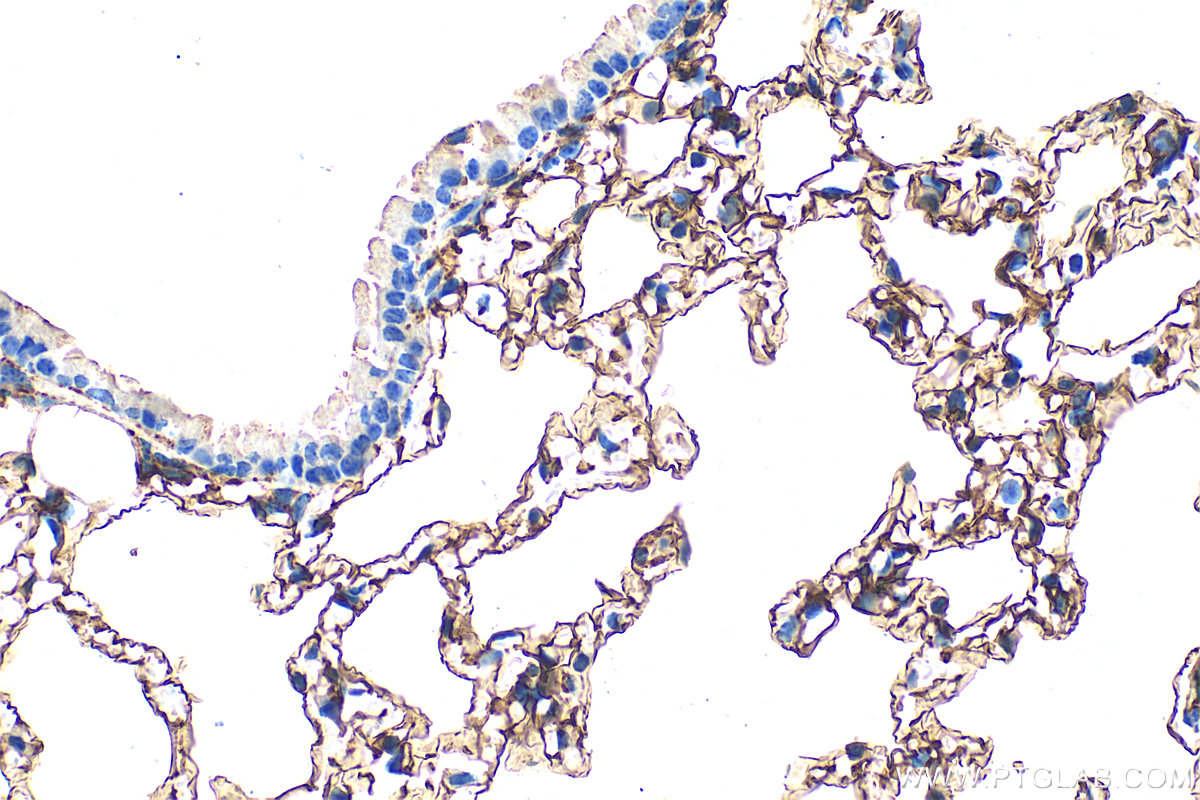

| Positive IHC detected in | mouse lung tissue, mouse kidney tissue Note: suggested antigen retrieval with TE buffer pH 9.0; (*) Alternatively, antigen retrieval may be performed with citrate buffer pH 6.0 |

| Immunohistochemistry (IHC) | IHC : 1:400-1:1600 |

33099-1-AP targets Podoplanin in WB, IHC, ELISA applications and shows reactivity with mouse samples.

Podoplanin was identified as a glycoprotein found in the cell membranes of glomerular epithelial cells (podocyte) (PMID: 9327748). It is a lymphatic marker because the expression of podoplanin has been detected in lymphatic but not blood vascular endothelium, and is useful as the marker of tumor-associated Lymphangiogenesis. Podoplanin has a function in developing testis, most likely at the level of cell-cell interactions among pre-meiotic germ cells and immature Sertoli cells. It may be involved in cell migration and/or actin cytoskeleton organization. When expressed in keratinocytes, PDPN induces changes in cell morphology with transfected cells showing an elongated shape, numerous membrane protrusions, major reorganization of the actin cytoskeleton, increased motility and decreased cell adhesion. It is required for normal lung cell proliferation and alveolus formation at birth. PDPN induces platelet aggregation. It does not have any effect on folic acid or amino acid transport and does not function as a water channel or as a regulator of aquaporin-type water channels.